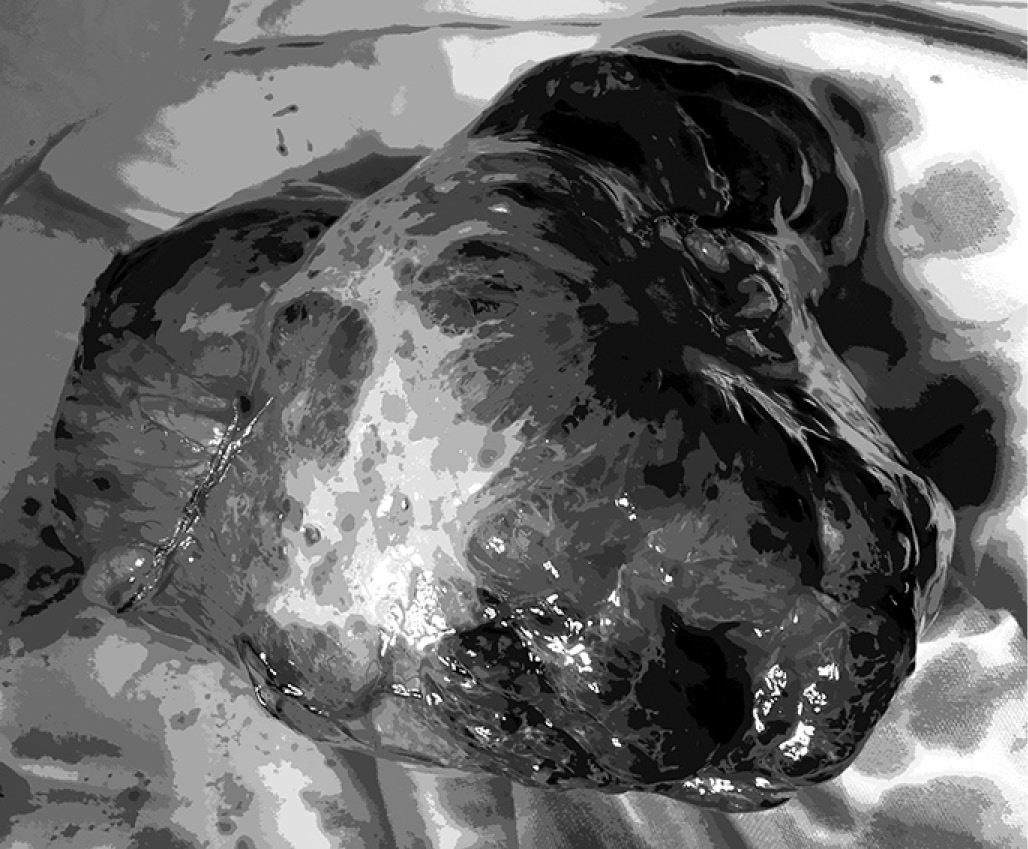

Макроскопическое описание удалённых анатомических структур: опухоль брюшной полости покрыта плотной капсулой, при пальпации – плотной консистенции, размерами 15×12×11 см (рис. 11), на разрезе – множественные кистозные полости и очаги некроза, заполненные темно-коричневым содержимым (рис. 12).

Рис. 11. Опухоль покрыта плотной капсулой, размерами 15×12×11 см

Рис. 12. Множественные кистозные полости и очаги некроза, заполненные тёмно-коричневым содержимым

В культе желудка, после его вскрытия, имеется подслизистое образование размерами 6×5×5 см, по структуре аналогичное первому (рис. 13).

Рис. 13. Подслизистое образование размерами 6×5×5 см